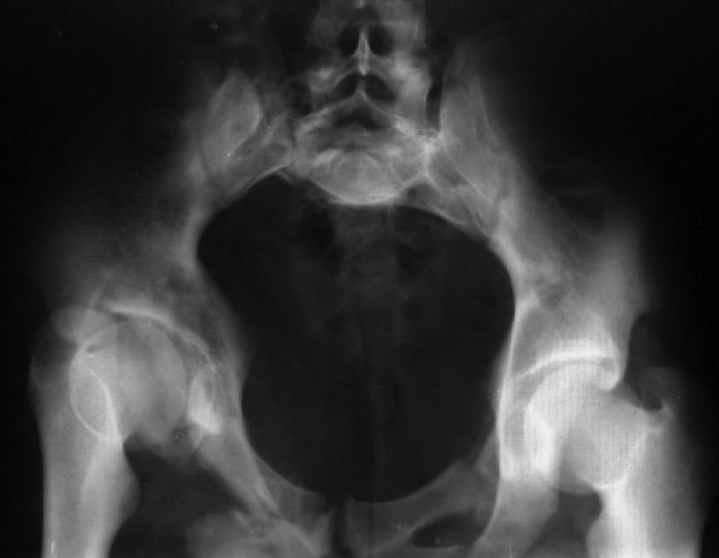

Уважаемые коллеги! Хотел-бы обсудить варианты лечения больной с застарелым переломом таза. Возраст 40 лет. Травма 11 месяцев назад. Главный травматолог Камчатского Военно-морского госпиталя Юрий Алексеевич Булахтин

У больного судя по всему вертикальная деформация таза. А каковы основные жалобы пациента и какие у него функциональные требования?

Для информации к размышлению о возможности исправления имеющейся деформации предлагаю похожий случай.